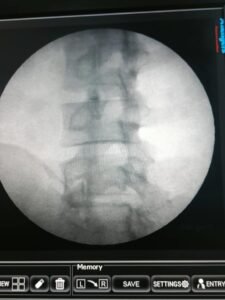

Once the PRP is prepared, it is injected directly into the affected facet joints under guided imaging, such as fluoroscopy or ultrasound, to ensure precise targeting. The growth factors and proteins present in PRP help reduce inflammation, promote tissue regeneration, and stimulate the production of new cells and collagen. The treatment process is minimally invasive, usually completed as an outpatient procedure, and requires minimal recovery time.